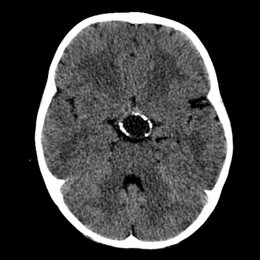

PREGUNTA 2 de 10

¿Cuál es el diagnóstico más probable de la siguiente imagen?

A)

quiste aracnoideo

B)

Quiste de la bolsa de Rathke

C)

craneofaringioma

D)

Silla turca vacía

E)

macroadenoma hipofisario